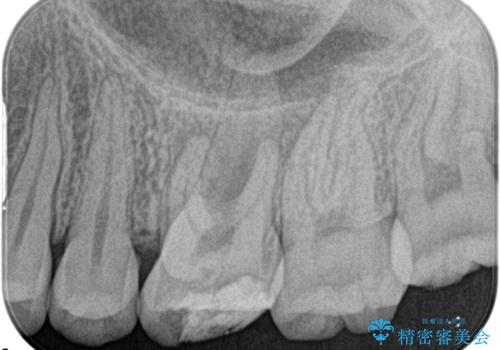

奥歯の根管治療

担当医 河口智英